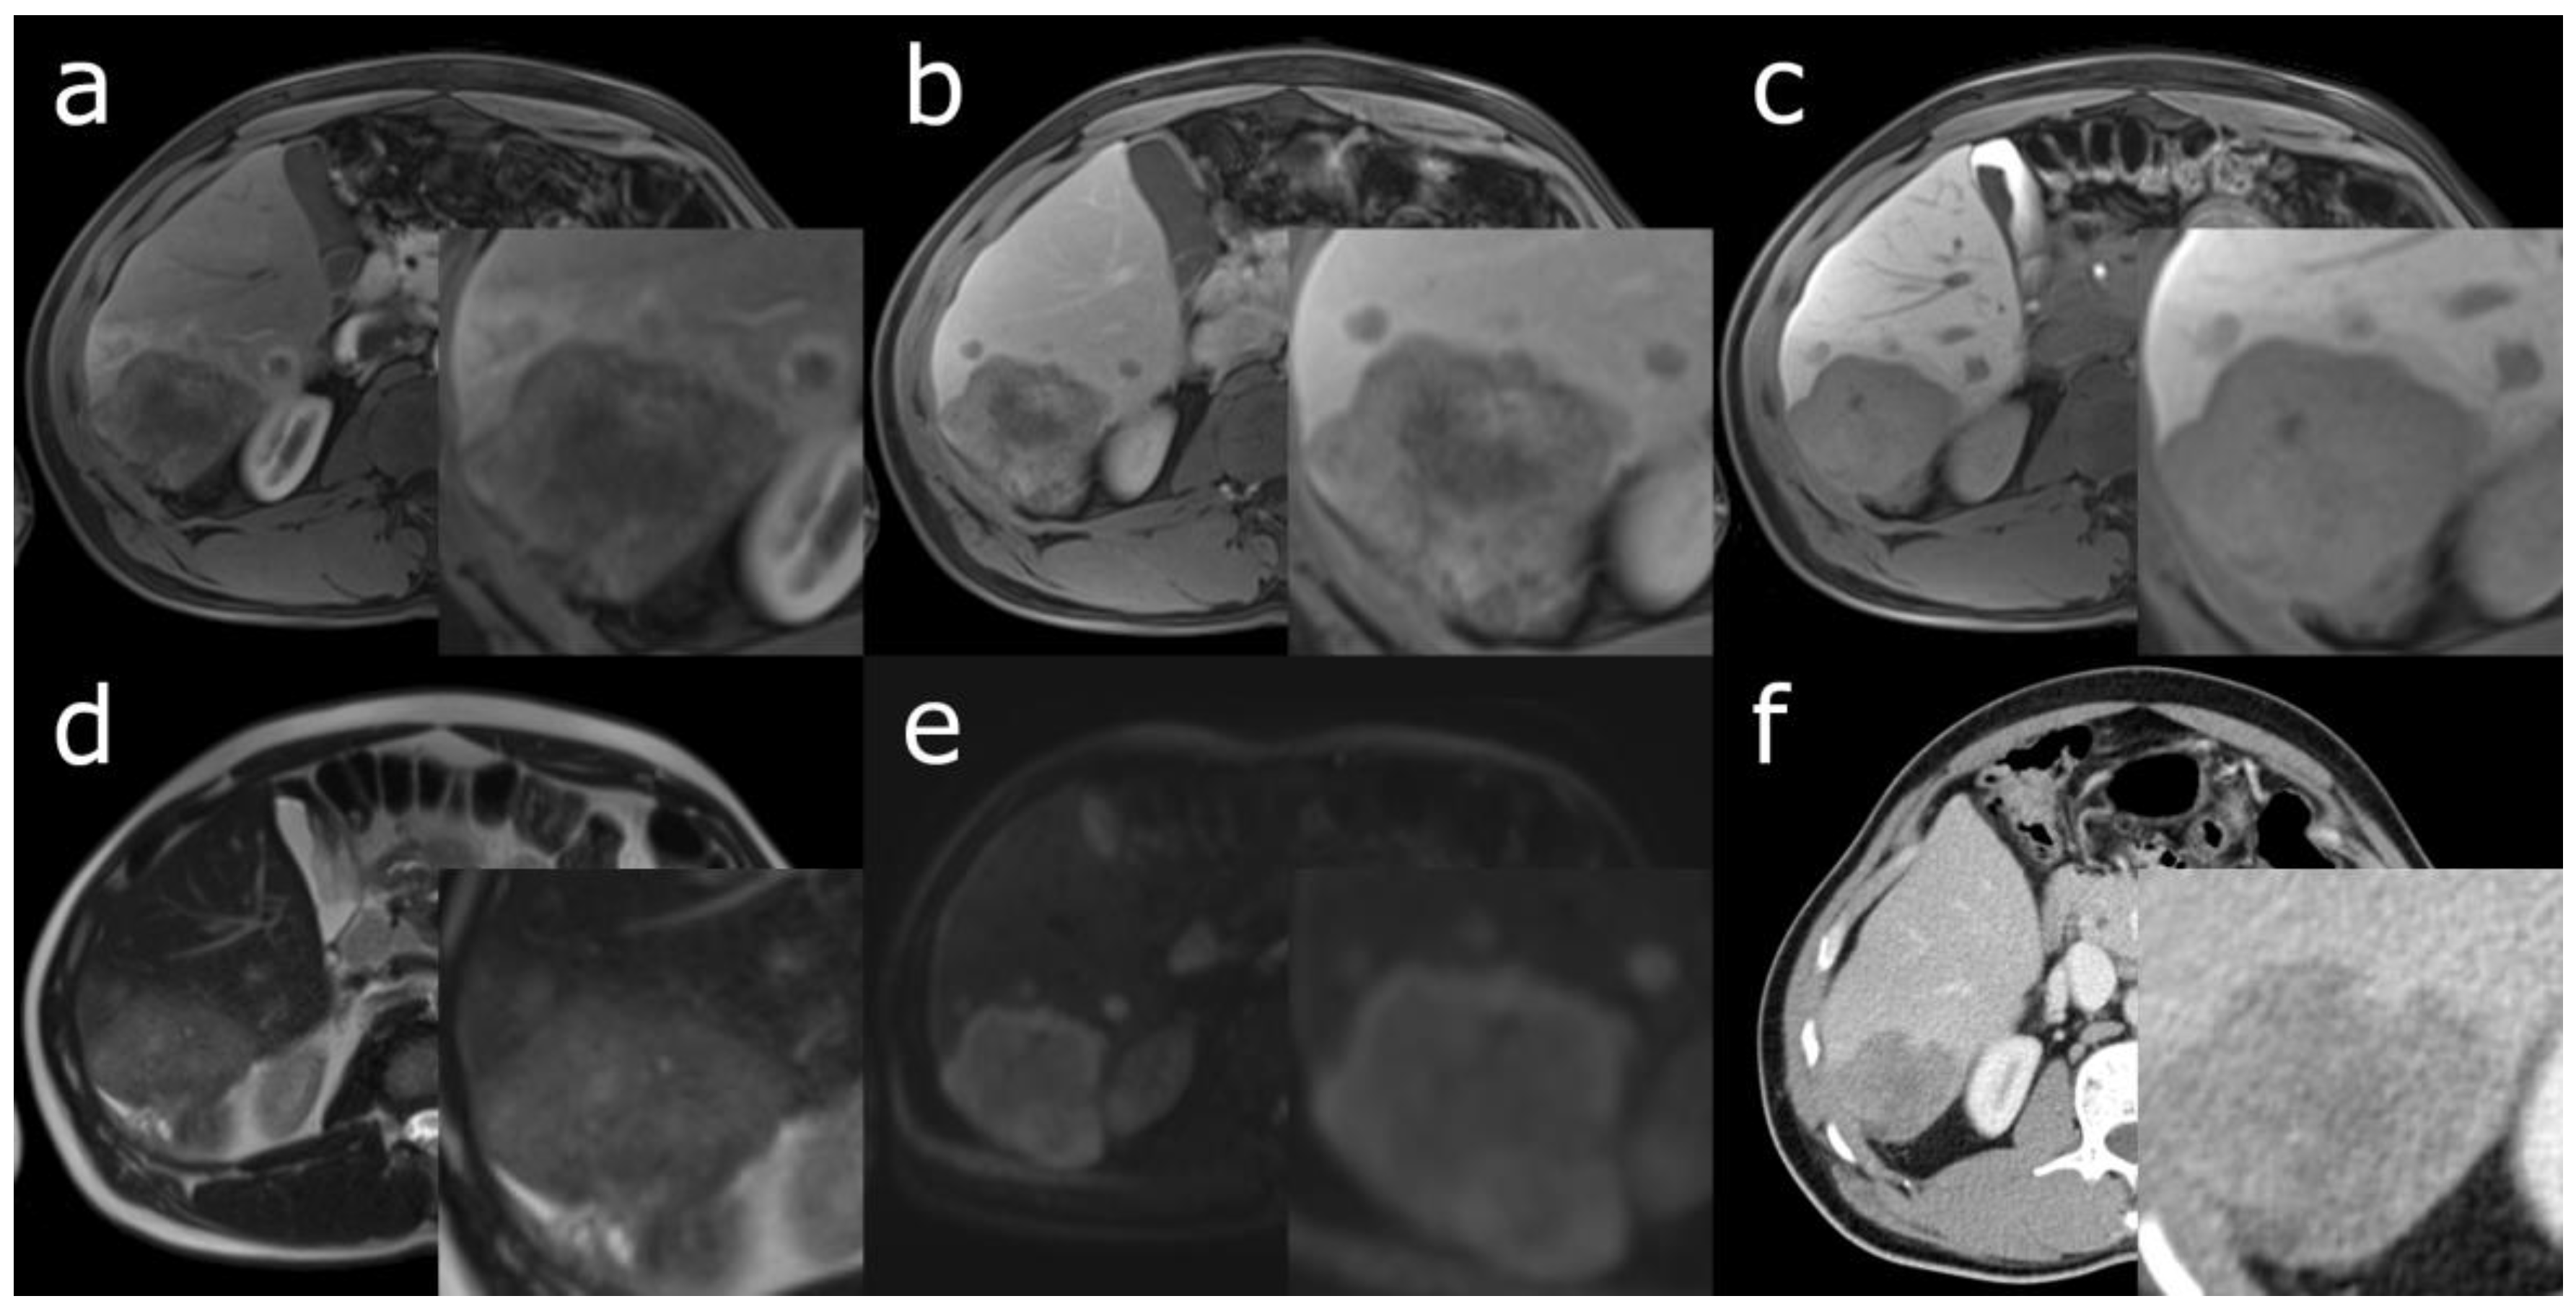

- Zhou, C.; Lu, X.; Wang, Y.; Qian, X.; Yang, C.; Zeng, M. Histopathological components correlated with MRI features and prognosis in combined hepatocellular carcinoma-cholangiocarcinoma. Eur. Radiol. 2022, 32, 6702–6711. [Google Scholar] [CrossRef] [PubMed]

- Park, S.H.; Lee, S.S.; Yu, E.; Kang, H.J.; Park, Y.; Kim, S.Y.; Lee, S.J.; Shin, Y.M.; Lee, M.G. Combined hepatocellular-cholangiocarcinoma: Gadoxetic acid-enhanced MRI findings correlated with pathologic features and prognosis. J. Magn. Reson. Imaging 2017, 46, 267–280. [Google Scholar] [CrossRef]

- Choi, S.H.; Jeon, S.K.; Lee, S.S.; Lee, J.M.; Hur, B.Y.; Kang, H.J.; Kim, H.; Park, Y. Radio-pathologic correlation of biphenotypic primary liver cancer (combined hepatocellular cholangiocarcinoma): Changes in the 2019 WHO classification and impact on LI-RADS classification at liver MRI. Eur. Radiol. 2021, 31, 9479–9488. [Google Scholar] [CrossRef]

- Fowler, K.J.; Sheybani, A.; Parker, R.A., 3rd; Doherty, S.; E, M.B.; Chapman, W.C.; Menias, C.O. Combined hepatocellular and cholangiocarcinoma (biphenotypic) tumors: Imaging features and diagnostic accuracy of contrast-enhanced CT and MRI. AJR Am. J. Roentgenol. 2013, 201, 332–339. [Google Scholar] [CrossRef] [PubMed]

- Zou, X.; Luo, Y.; Morelli, J.N.; Hu, X.; Shen, Y.; Hu, D. Differentiation of hepatocellular carcinoma from intrahepatic cholangiocarcinoma and combined hepatocellular-cholangiocarcinoma in high-risk patients matched to MR field strength: Diagnostic performance of LI-RADS version 2018. Abdom. Radiol. 2021, 46, 3168–3178. [Google Scholar] [CrossRef]

- Yoon, J.; Hwang, J.A.; Lee, S.; Lee, J.E.; Ha, S.Y.; Park, Y.N. Clinicopathologic and MRI features of combined hepatocellular-cholangiocarcinoma in patients with or without cirrhosis. Liver Int. 2021, 41, 1641–1651. [Google Scholar] [CrossRef] [PubMed]